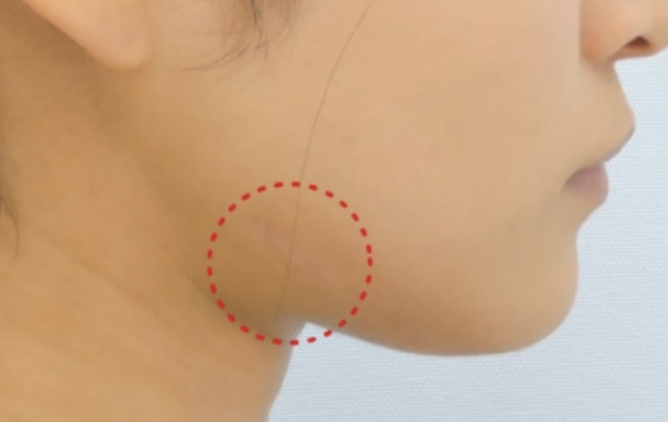

骨切り量が非常に大きい

オトガイ神経を剥離して下顎骨を広範囲に露出し、神経の上下からアプローチするため、骨切り範囲がオトガイ部先端から下顎角直前におよび、切除幅8㎝~10㎝、全長14cm~16cmと非常に大きい。

スムーズなカーブを描く

骨切りが可能

骨切りカッターを骨面に垂直に当てることが出来るため、スムーズで自然なカーブを形成出来る。

左右差が少ない

術者の利き手に影響されないため左右対称に骨切り出来る。

安全性が非常に高い

顔面神経・顔面動脈とは離れた位置での操作であることと、下顎角裏側の翼突筋群を十分に剥離することが出来るため、安全性が非常に高い。また、手術中に透明3-D立体模型にて下歯槽神経管の位置を確認しながら骨切りするため、下歯槽神経を損傷する可能性が殆どない。

腫れが非常に少ない

骨切り部分のみを剥離するため腫れが最小限に抑えられる。